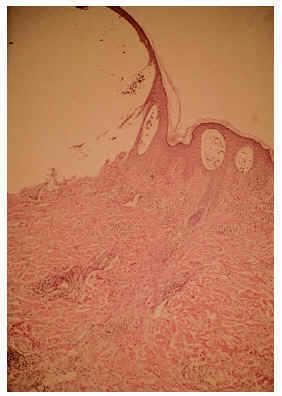

El estudio histopatológico de una lesión de contenido líquido reveló una ampolla subepidérmica, con un infiltrado perivascular en dermis superficial con predominio de eosinófilos, que también se hallaban en el interior de la ampolla (fig. 2). Con la inmunofluorescencia directa se encontraron depósitos de IgG y C3 a nivel de la membrana basal (fig. 3) y la indirecta demostró anticuerpos frente a la membrana basal a títulos de 1/80. La inmunofluorescencia directa del lado sano fue negativa.

Fig. 2.--Detalle de un lateral de la ampolla, con infiltrados perivasculares de eosinófilos y en el interior de la cavidad (HE, x100).